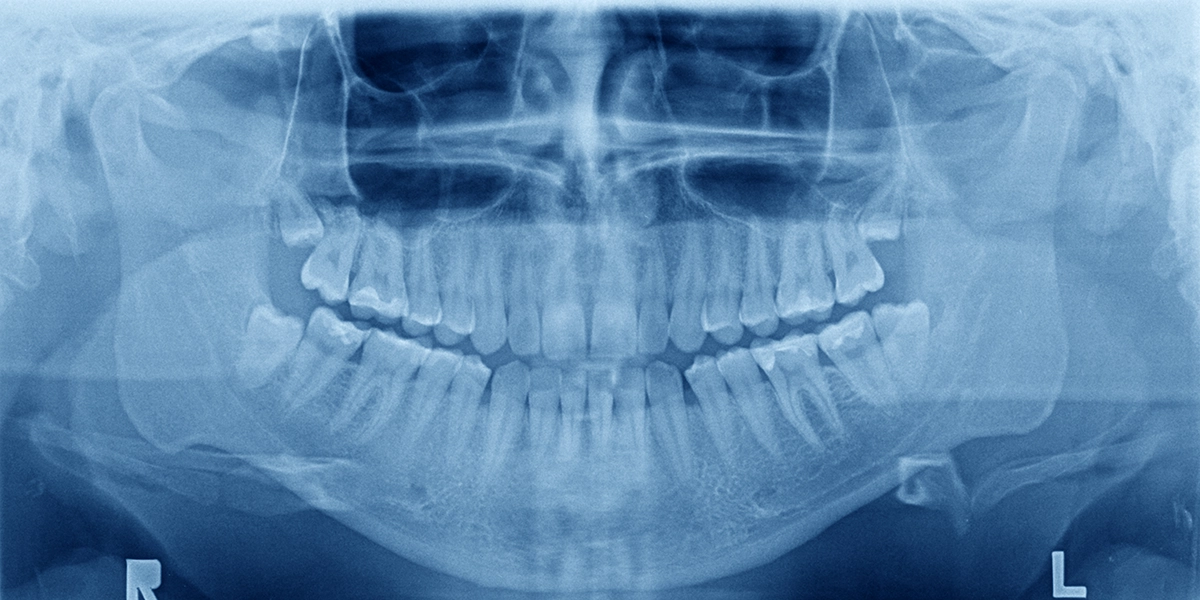

親知らずの抜歯を安全に行うためには、事前の精密な診査が不可欠です。通常のレントゲン撮影では平面的な情報しか得られませんが、歯科用CTを使用することで、親知らずの3次元的な位置、根の形態、周囲の重要な構造物との関係を正確に把握できます。

下顎の親知らずの近くには「下歯槽神経」という太い神経が通っています。この神経は下唇や顎の感覚を司っており、抜歯時に損傷すると、唇や顎の感覚が麻痺する可能性があります。CT検査により、親知らずの根と神経との距離を正確に測定し、神経損傷のリスクを事前に評価できます。

上顎の親知らずの上方には「上顎洞」という鼻とつながった空洞があります。上顎洞と親知らずの根が近接している場合、抜歯時に上顎洞と口腔内が交通してしまう「口腔上顎洞瘻」が生じるリスクがあります。CT検査でこの距離を確認し、適切な抜歯方法を計画します。